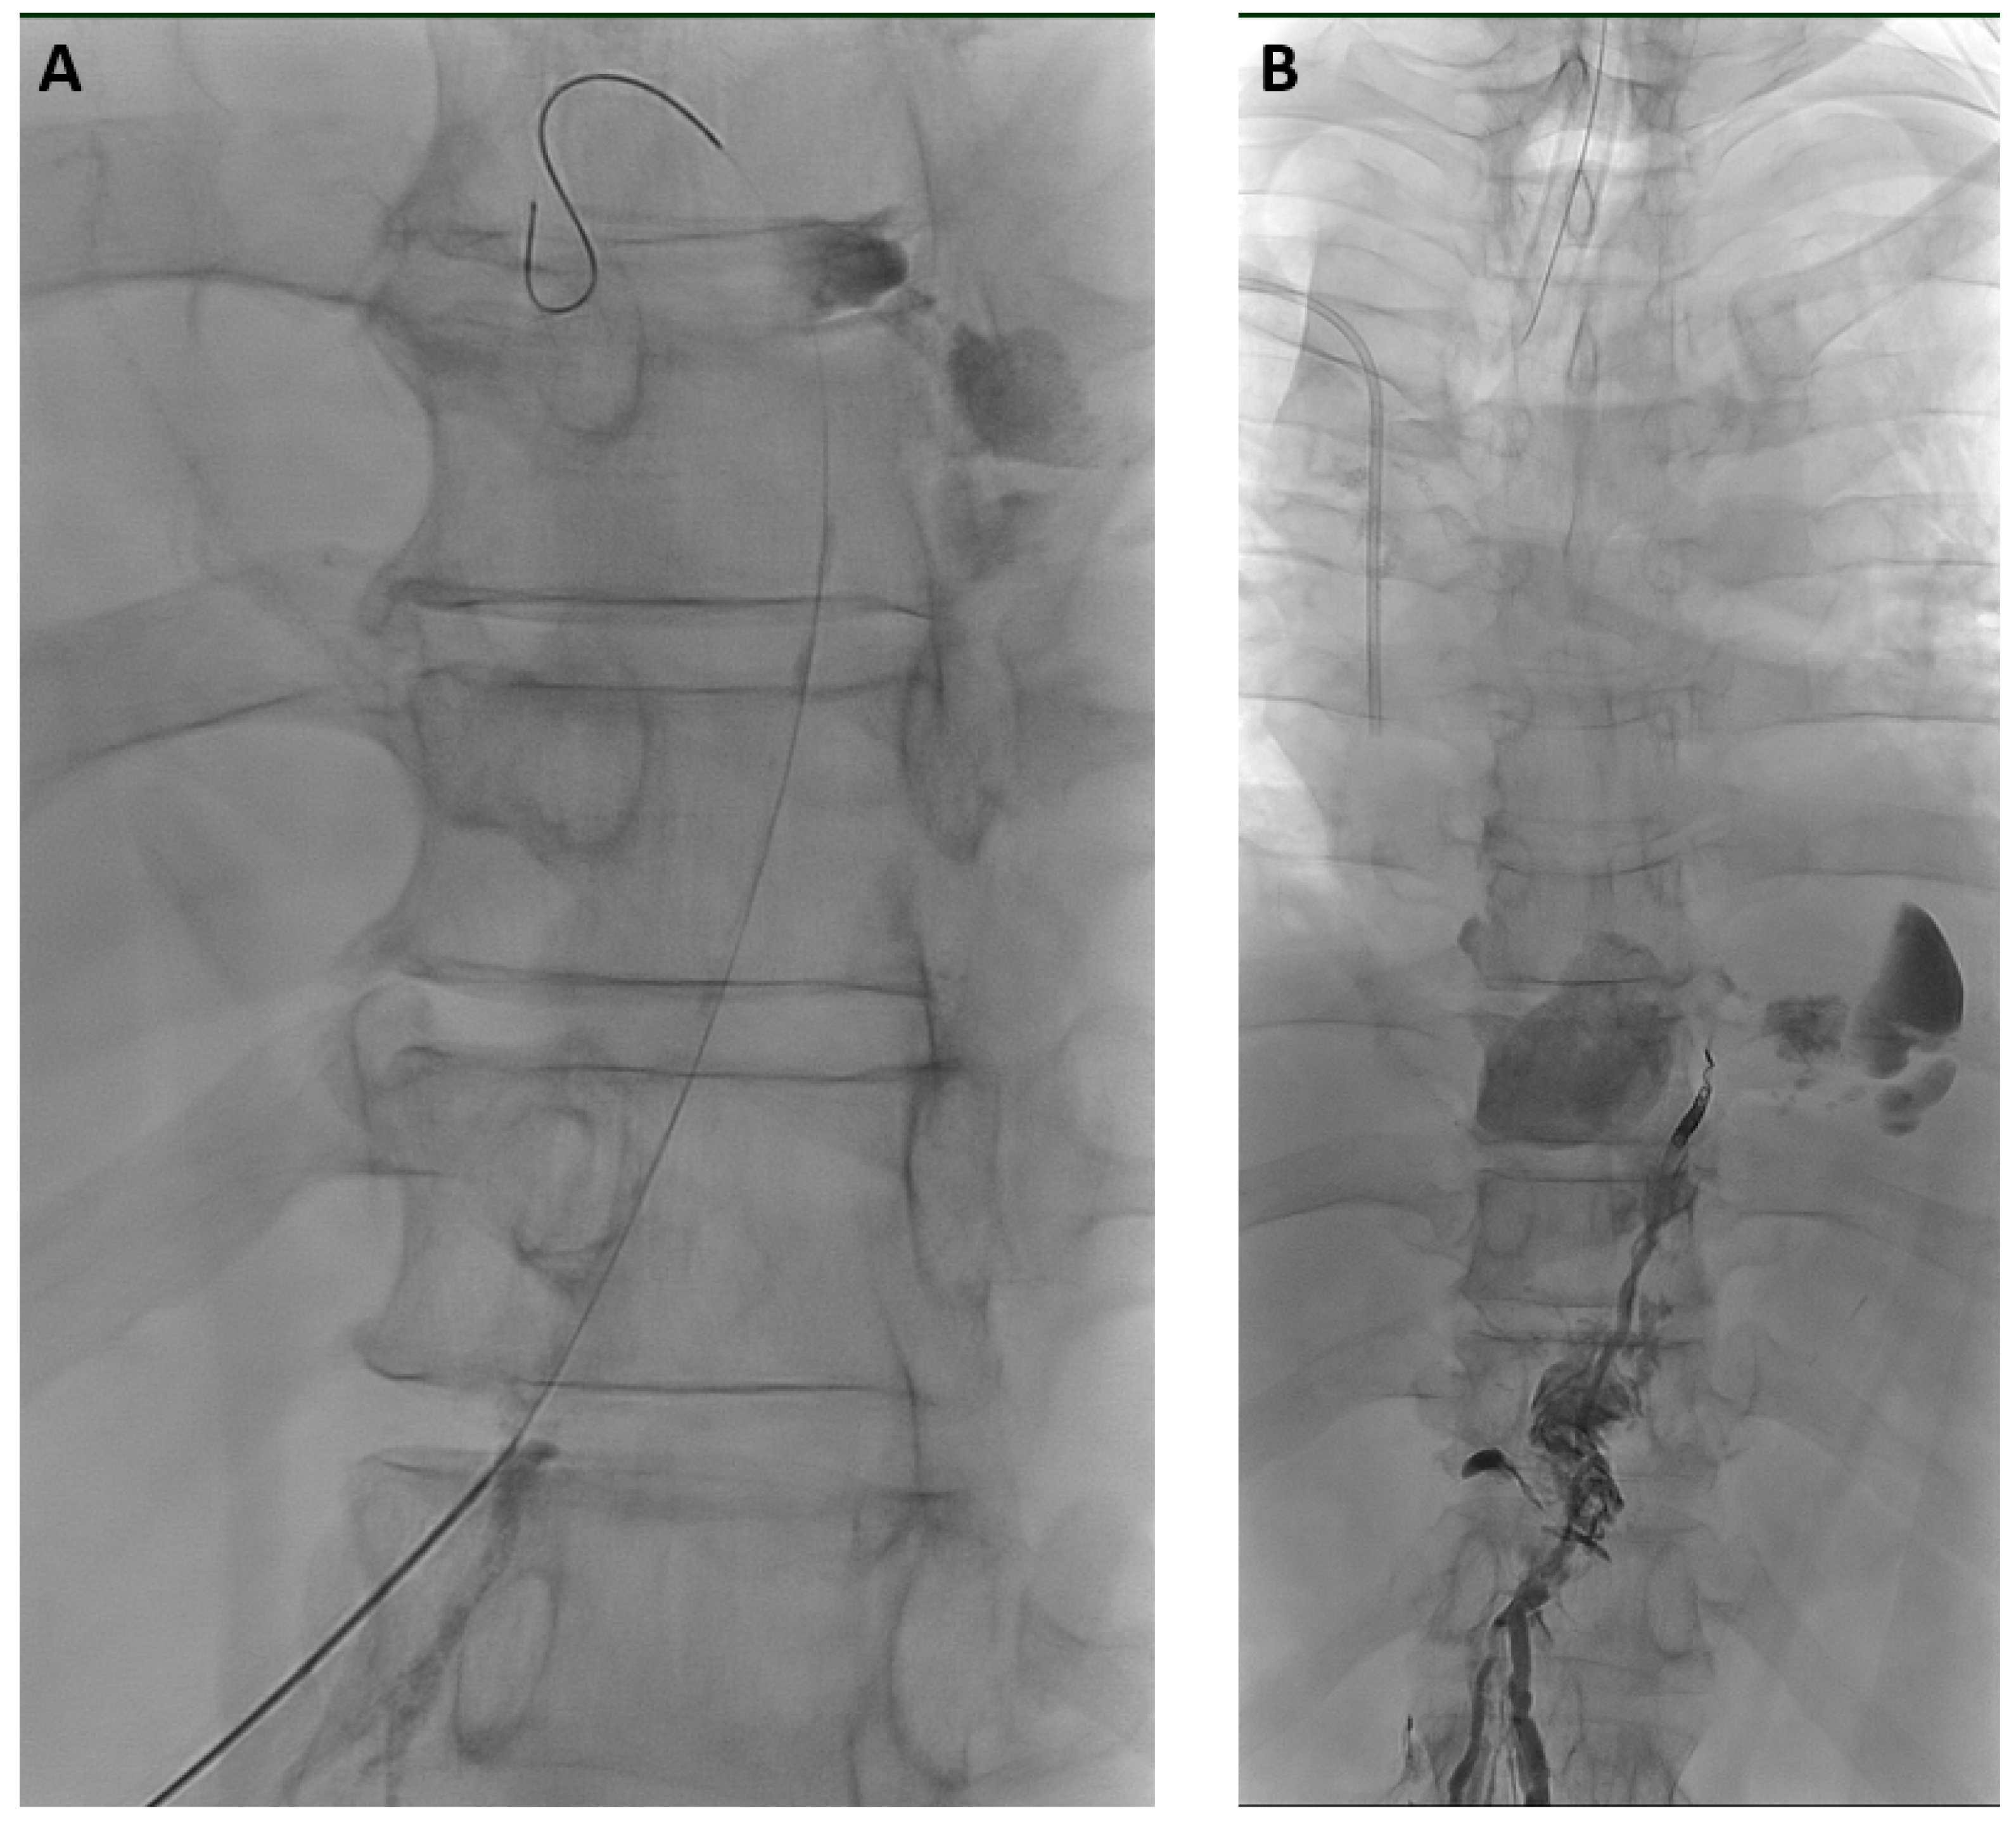

Figure 2.

71-year-old man with bilateral chylothorax after esophagectomy. (A) X-ray lymphangiography demonstrated transection of the thoracic duct in the lower thorax with active leakage of contrast agent. After puncture of the thoracic duct, the inserted micro-wire already exits the thoracic duct at the leakage-site. (B) After thoracic duct embolization with micro-coils and a mixture of NBCA/iodized oil (ratio 1:2) leakage ceased immediately without recurrence or clinical sequelae over a follow-up time of 2.5 years.